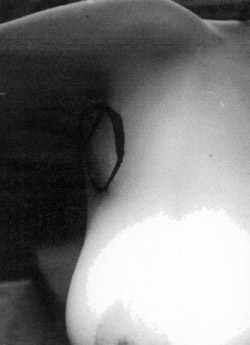

Eικόνα 1. Στην εικόνα φαίνεται

εντός του περιγράμματος η διόγκωση στη μασχαλιαία περιοχή.